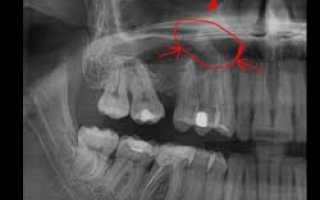

Рентген

При остром одонтогенном гайморите на рентгеновском снимке можно увидеть утолщение слизистой оболочки пазухи, уменьшение пневматизации и чёткий уровень жидкости — эти признаки указывают на выраженный воспалительный процесс. Также при обзорном снимке полости рта или прицельной рентгенографии заинтересованного зуба могут быть обнаружены признаки пульпита, периодонтита и нагноения кисты.

Проявлением длительного одонтогенного гайморита может быть незначительное уменьшение уровня заполнения воздушных полостей пазухи, при этом обнаруживаются незначительные воспалительные изменения в зубах и окружающих их тканях.